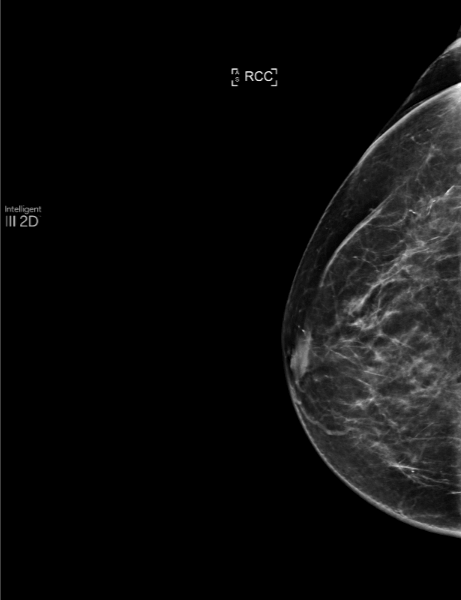

By analyzing the previous 2022 review with MammoScreen, the mass, still smaller and less spiced, is detected by the software with a score of 5 on both incidences.